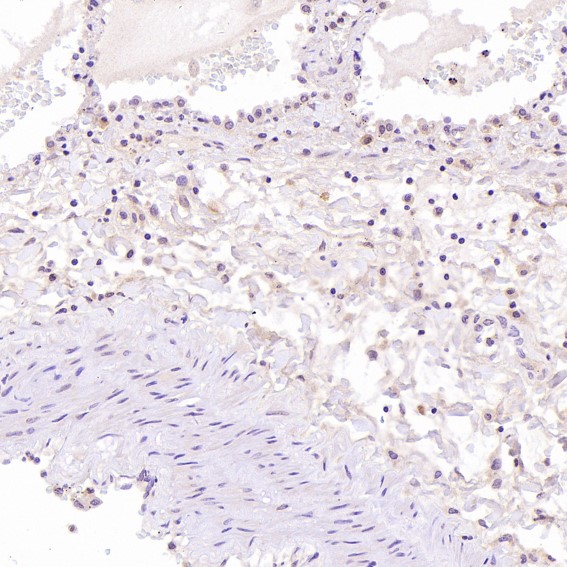

Immunohistochemical analysis of paraffin-embedded Human liver cancer, using the Antibody at 1:200 dilution.